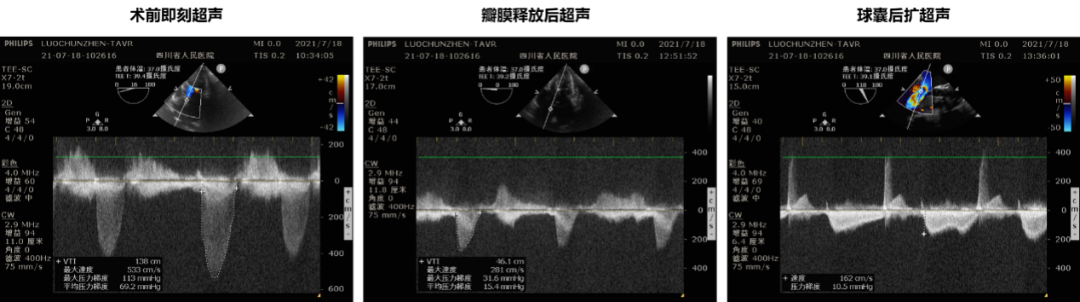

患者为55岁女性,左心显著增大、心功能IV级、CKD3期、营养不良,一般情况差。超声提示:主动脉瓣增厚,瓣叶开放显著受限,关闭不佳;二尖瓣稍增厚,后瓣动度差,开放稍受限。心包腔少量积液,主动脉瓣前向血流加速Vmax=4.8m/s,PGmean=62mmHg。超声提示主动脉瓣重度狭窄伴中度反流,二尖瓣轻微狭窄,三尖瓣轻度反流。

术后超声心动图显示:主动脉瓣人工瓣膜前向1.6m/s,平均跨瓣压差由瓣膜植入前的69mmHg降至约10.5mmHg,微量反流,使用25mm球囊后扩,之后平均跨瓣压差为8mmHg,无返流,手术效果良好。